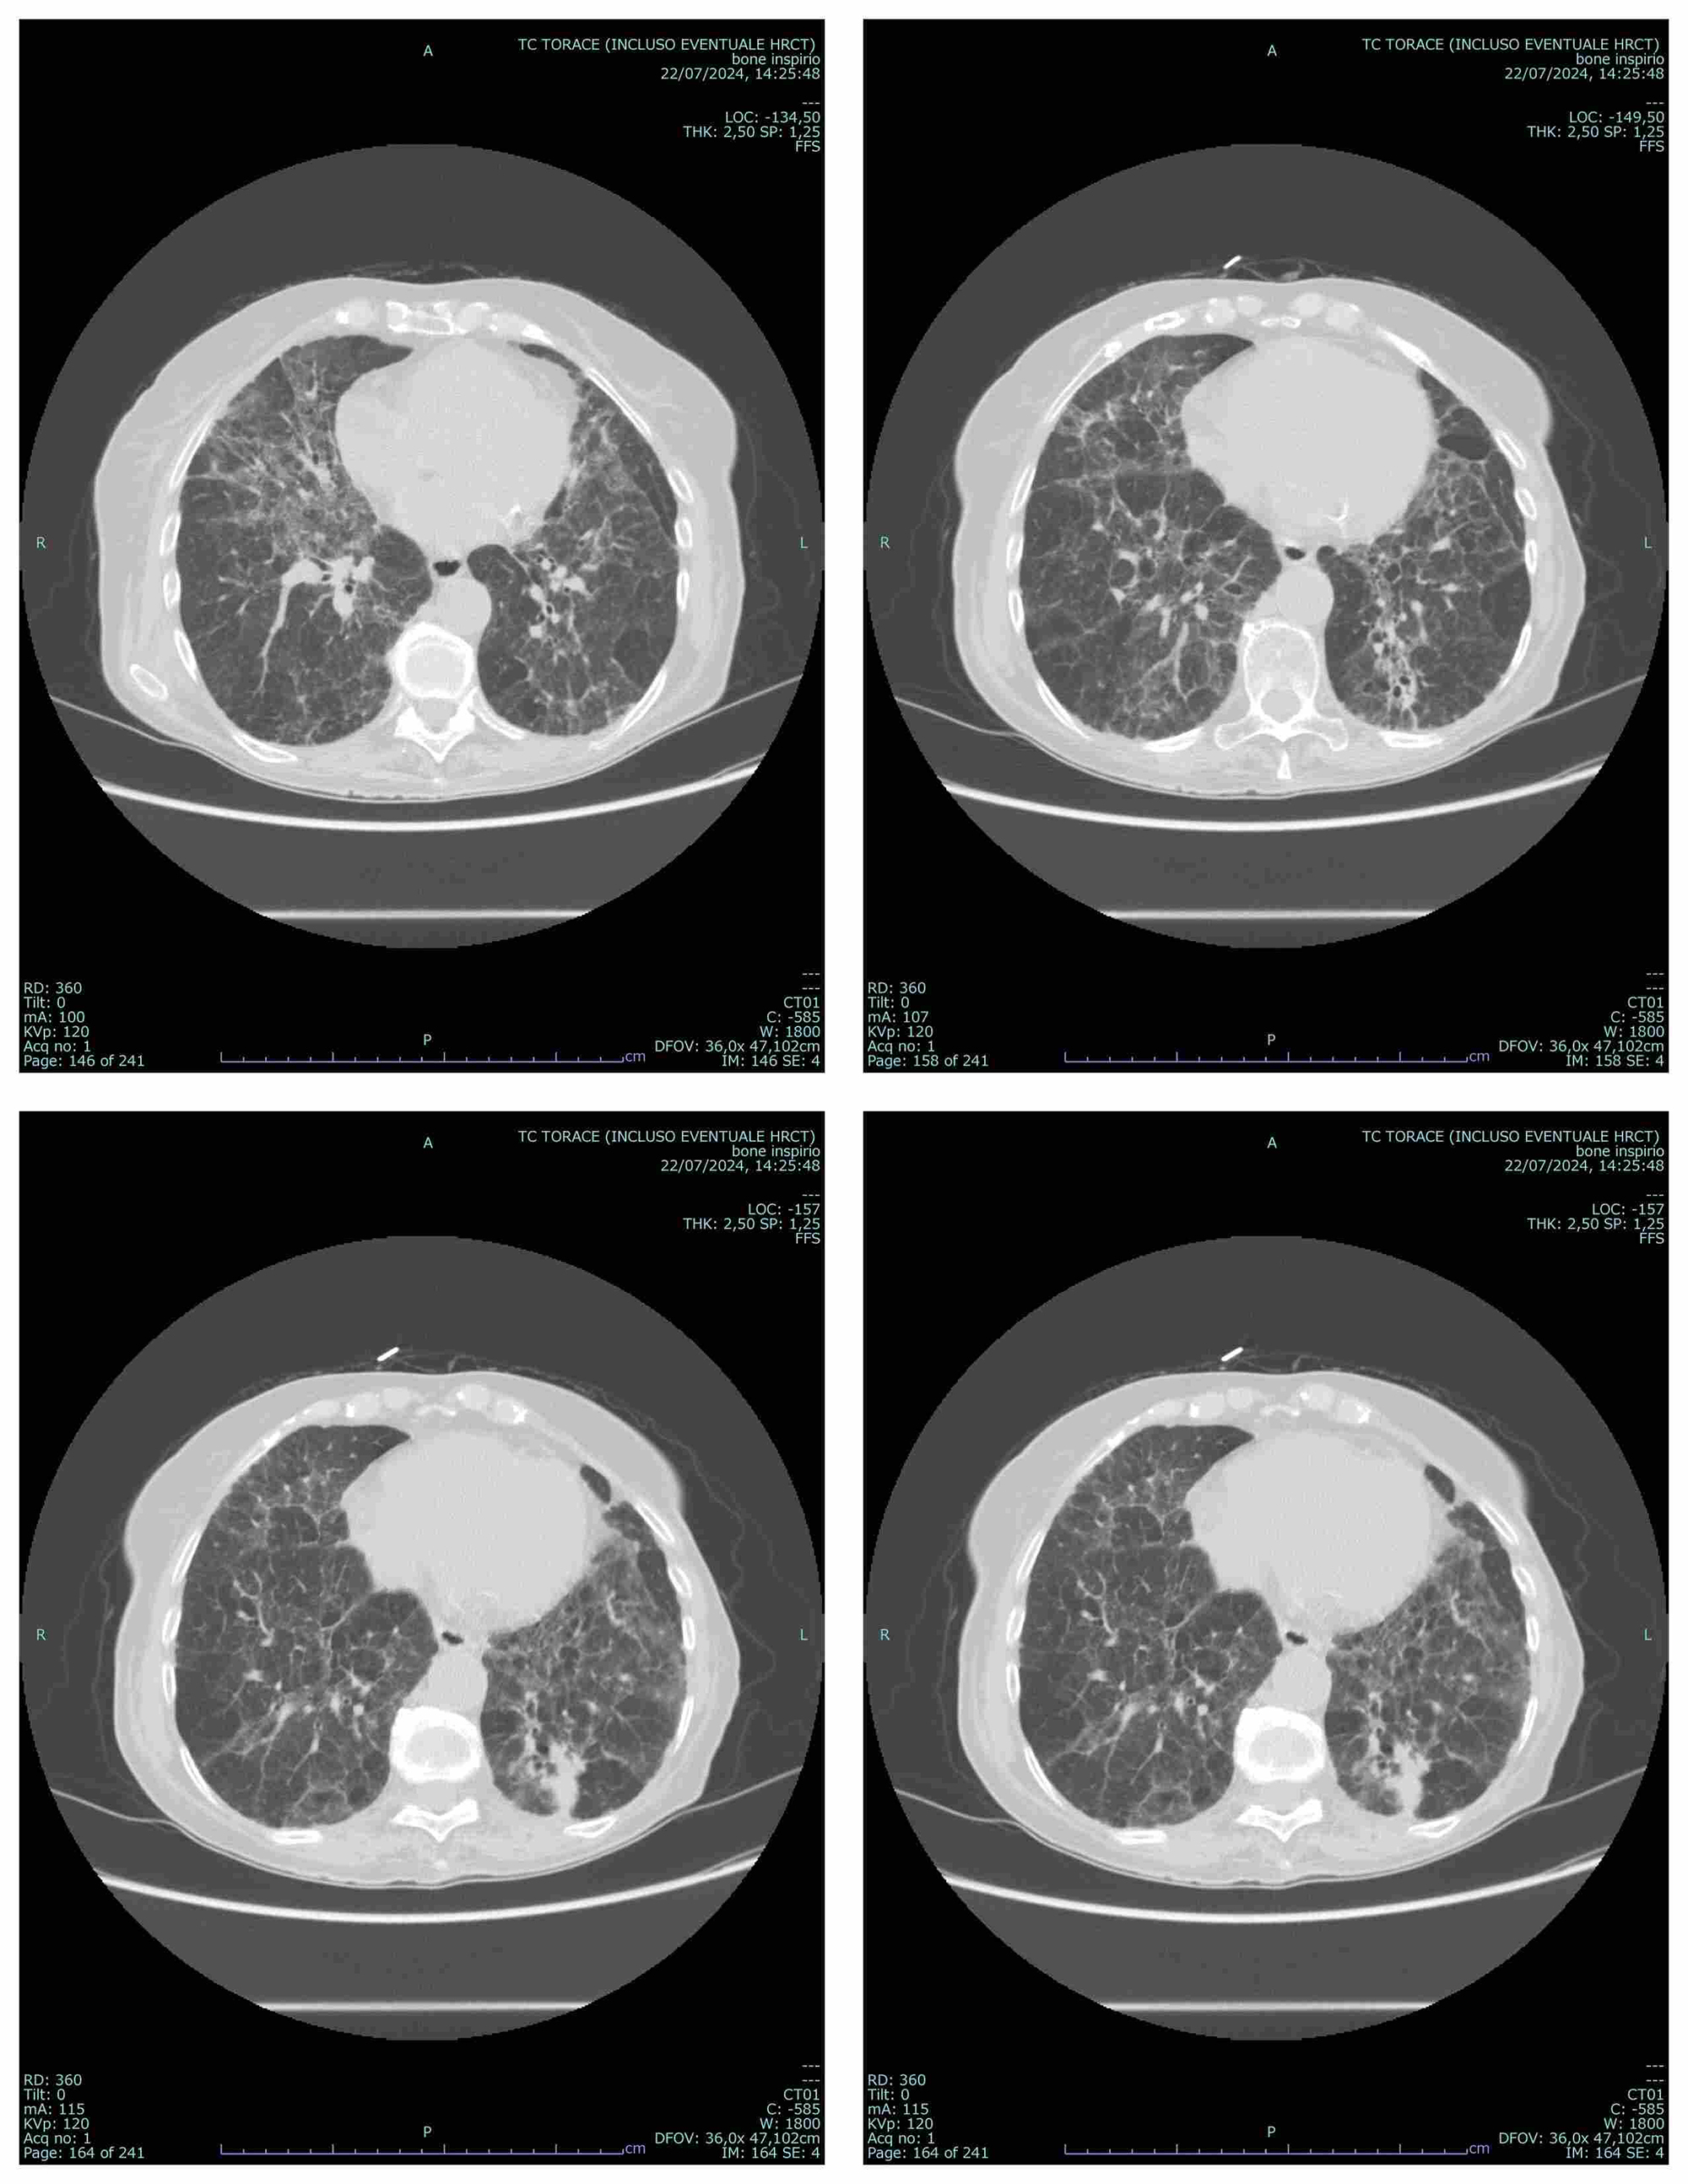

PO:34:207 | When the Lungs Speak in Squeaks: Chronic Bird-Related HP in SSc-ILD with Incidental Lymphoma

Mariagrazia Nuara1, Marco De Pinto2, Amelia Spinella2, Stefania Cerri1|2, Enrico Clini1|2, Dilia Giuggioli1|2 | 1Università degli Studi di Modena e Reggio Emilia, Italy; 2AOU, Policlinico di Modena, Italy